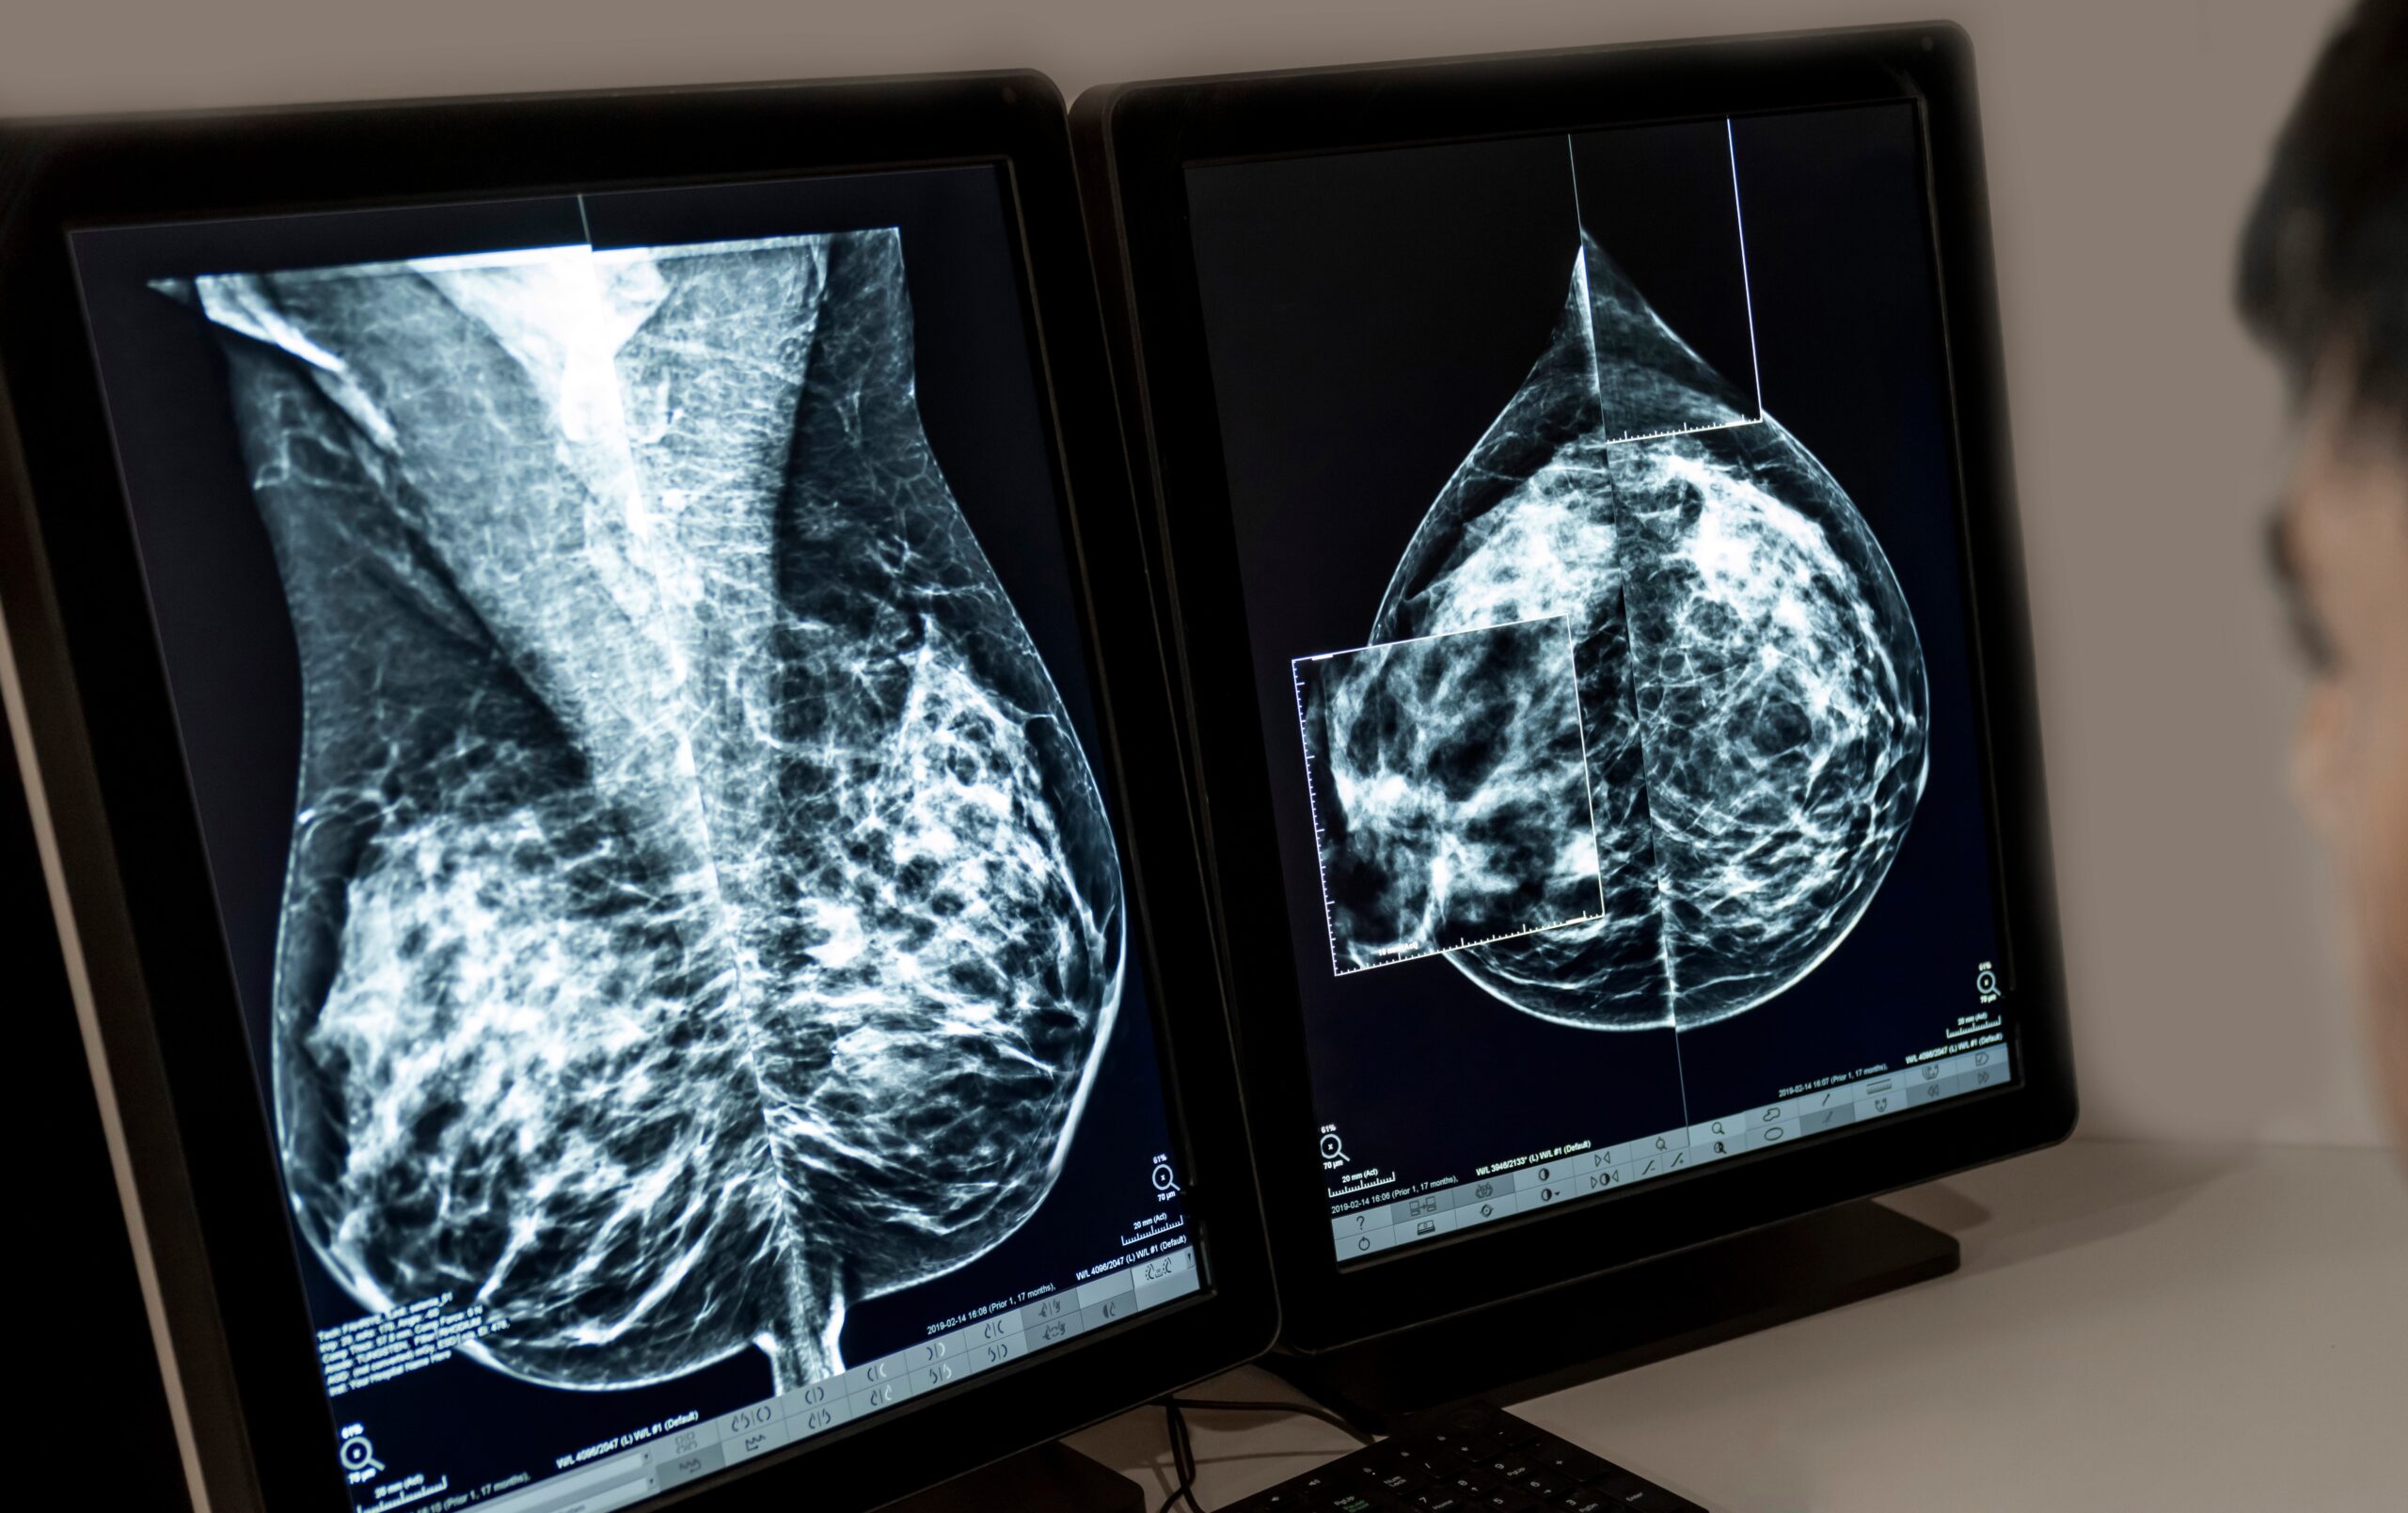

Entre as mulheres, o câncer de mama permanece como o mais incidente no país.

Adobe Stock

Entre as mulheres, o câncer de mama permanece como o mais incidente no país, com números próximos de 80 mil novos casos por ano —tendência semelhante à observada em países desenvolvidos.